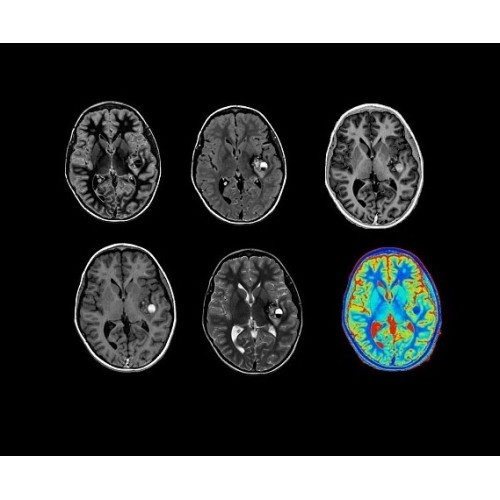

В систему SIGNA PET/MR встроены запатентованные детекторы кремниевого фотоумножителя (SiPM) и сверхчувствительные кристаллические сцинтилляторы на основе лютеция толщиной 25 мм. Благодаря этому обеспечивается исключительная чувствительность и возможность использования времяпролетной диагностики (TOF).

Кроме того, в результате использования технологии TOF и инновационной технологии реконструкции Q.Clear вы сможете добиться прекрасного соотношения сигнал/шум. А благодаря технологии нулевого времени эхо (ZTE) визуализировать костную структуру без ионизирующего излучения. Все эти разработки для улучшения качества сканирования и точности анализа помогут вам использовать весь потенциал ПЭТ/МРТ.

• TurboTOF — инновационная технология позволяет корректировать коэффициент затухания сигнала и минимизировать потери анатомических данных, создавая МР-систему для количественной визуализации.

• Q.Clear — в основу технологии легли накопленные знания о том, как минимизировать помехи при реконструкции и получить четкое изображение. При значительном улучшении качества изображения сохраняется точность расчетов. Сочетание технологии TOF и реконструкции Q.Clear — ваш надежный помощник для получения точных и достоверных данных.

• Специальный пакет приложений для измерения и сравнения объемных изображений ЦНС с нормами поможет вам в диагностике нейродегенеративных заболеваний, а дополнительные инструменты визуализации — в постановке точного диагноза с помощью бета-амилоидов и радиоизотопных маркеров ФДГ.